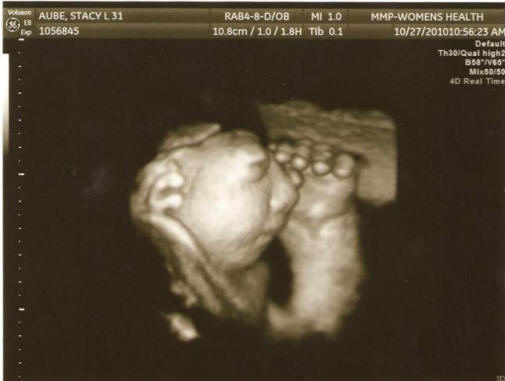

Fotografije iz odprtih virov, vključenih v preiskavo strokovnjaki so primerjali zdravstveno kartoteko nosečnic od 27 območja, registrirana v predporodnih ambulantah, kjer študirajo so delali, kot so bili bolni, ali so pili alkohol, droge ali prekajeni izdelki, na kakšnem območju so živeli in iz česa vir je pil vodo. Navsezadnje vladni uradniki sklenil, da niso mogli ugotoviti “pogojev ali razlogov” tega pojava. “Rezultati so bili razočarajoči, vendar ne povsem nepričakovano, priznani znanstvenik Jim Kucik (Jim Kucik), ki je sodeloval v raziskavi. – Običajno takšne prirojene napake povzročajo kombinacija dejavnikov, ki jih je zelo težko zaznati. Ne mogoče je, da je vse to samo naključje. ” In tu je genetsko svetovalka Susie Ball verjame, da v treh okrožjih Država Washington ima nekaj težav, ki bi jih morali imeti več pozornosti, da bi ženske zaščitile v prihodnosti v rodni dobi. Pozor, šokantna fotografija.

Fotografija iz odprtih virov “Ne bi rad prestrašil ljudi, ampak to, kar se dogaja, me vznemirja, “je poudarila. – Prejeto od informacije o medicinskem osebju bi morale biti široko objavljene, da ženske v rodni dobi sprejmejo vse potrebne ukrepe preprečiti razvoj te patologije. Za začetek jim svetujem vzemite folno kislino. ” Znanstveniki so rezultate že prebrali prejšnje študije, ki so prepoznale potencialne dejavnike tveganje za razvoj anencefalije: nizka prehranska folata kisline, izpostavljenost pesticidom in onesnaževanju pitne vode nitrati.